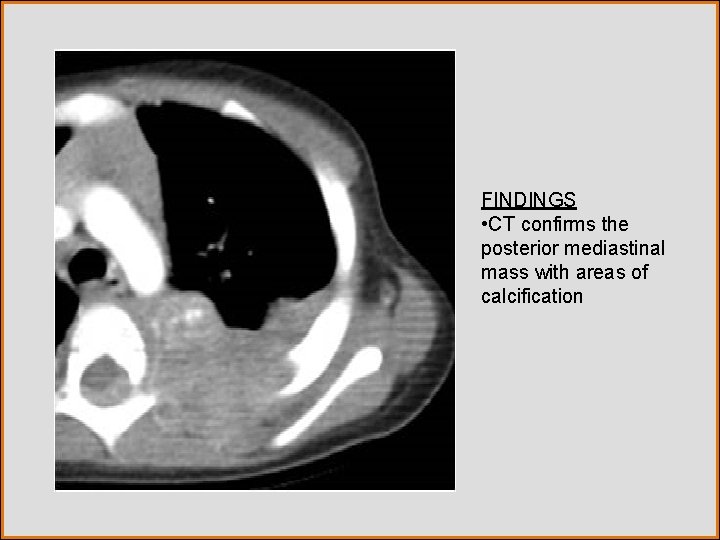

Case History • A CT was performed

Test Your Diagnosis What is the most likely diagnosis? a. Chondrosarcoma b. Thoracic neuroblastoma c. Bronchogenic cyst d. Paraspinal abscess e. Thoracic aortic aneurysm

FINDINGS • CT confirms the posterior mediastinal mass with areas of calcification